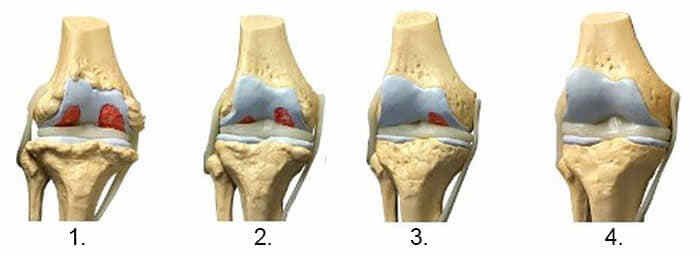

Суглоби

1. Недолік поживних речовин в суглобі. Хрящова тканина руйнується.

2. Відновлення хрящової тканини в суглобі через 2 тижні використання капсул Ortorion.

3. Відновлення хрящової тканини суглоба через 3 тижні застосування капсул Ortorion.

4. Здоровий суглоб після одного курсу капсул Ortorion.

На зображенні нижче показана типова картина відновлення колінного суглоба.